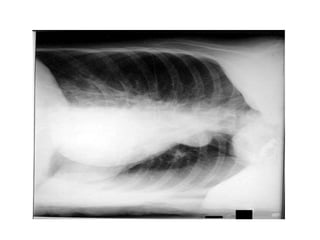

Lateral View

Position

Seen in : ant mediastinal

masses, encysted pleural fluid, post

basal consolidation